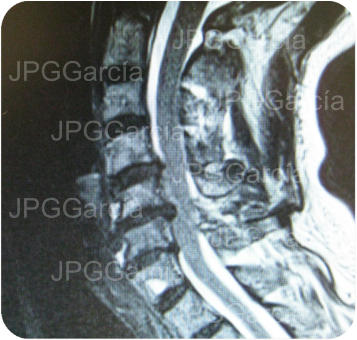

Tratamiento microquirúrgico de hernia extruida cervical con mielopatía

Estudios de control postquirúrgico radiográfico y de resonancia magnética